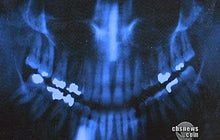

Prevett's 10 amalgams were replaced with newer composite fillings.

Amalgam is half silver and other metals and half mercury. It's more durable and cheaper than composite, a mixture of plastic and glass.